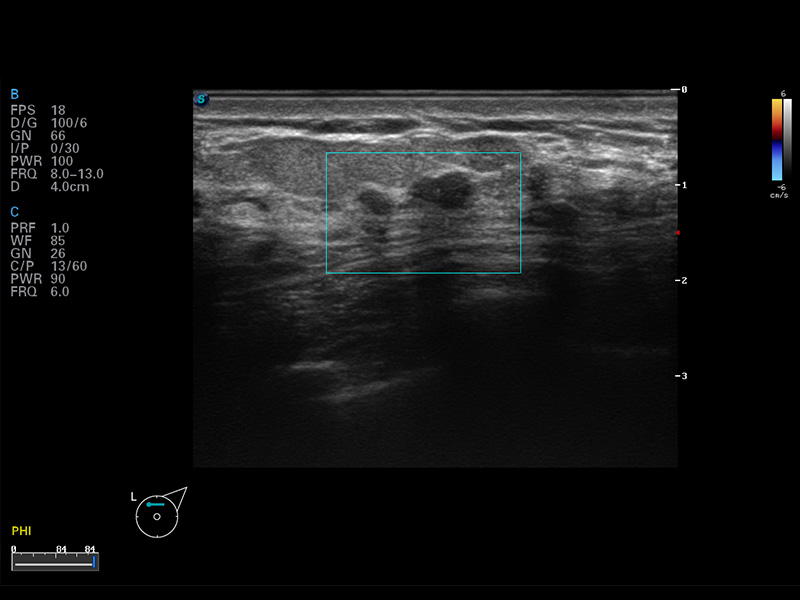

谐波成像